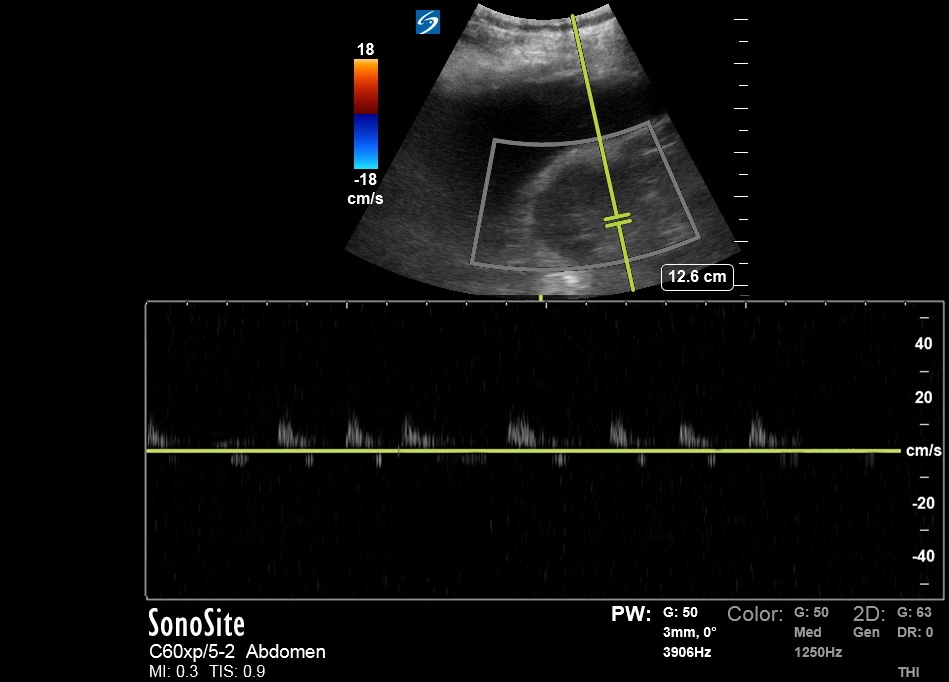

Bedside US done ~2 hours prior to RHC:

Bedside US done ~2 hours prior to RHC:

Another HV Doppler: